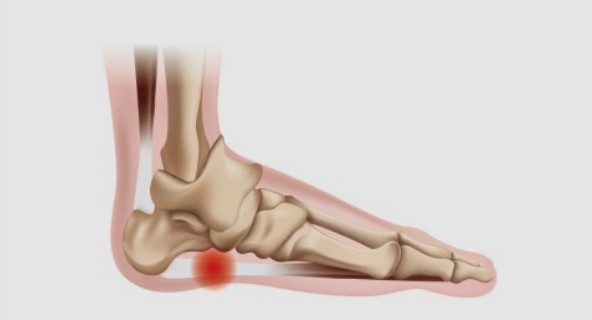

족저 근막염은 발바닥에 위치한 족저근막에 염증이 생기는 질환으로, 발꿈치에 통증을 유발합니다. 주로 하루 중 첫 번째 걸음에서 통증이 심하게 나타나며, 장기간 서 있거나 걷는 것에 어려움을 겪을 수 있습니다. 과도한 운동이나 비만, 잘못된 신발 착용 등으로 발병할 수 있습니다.

족저 근막염의 가장 흔한 증상은 발꿈치 통증입니다. 첫 걸음을 디딜 때 통증이 가장 심하며, 일상적인 활동 중에도 통증이 발생할 수 있습니다. 통증은 발꿈치 안쪽에서 느껴지는 경우가 많습니다.